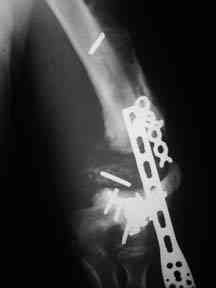

Attached are x-rays of a 21 year old male who is 3 years out from multiple injuries sustained in a motorcycle accident.

This was initially an open injury. Several attempts were made to fix this fracture at a nearby teaching facility. The most recent procedure was one year ago. His fixation failed last January. At that time he was told that he would have to wait for another doctor to care for him (rotation of residents I presume). No history of infection. Non-smoker. Due to his head injury his employment options are limited. He is capable of driving a truck if he had a functioning arm.

This is his non-dominant arm. He has a compete radial nerve palsy which has never been addressed. All previous humeral surgeries were done via a lateral approach.

I removed the floating hardware via the lateral approach through cement-like scar. Cultures and path were negative. The distal humeral segment, not surprising, is completely disvascular. Soft tissues will support further reconstruction via anterior or posterior approaches.

Any thoughts on the reconstructive options?